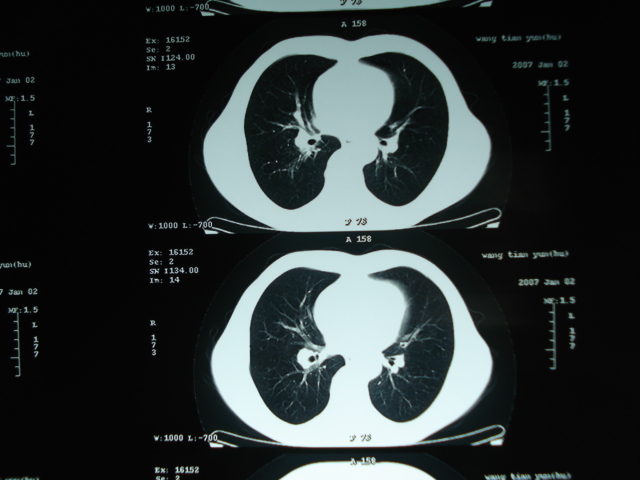

以下是引用狙击手在2007-4-18 20:17:00的发言:[br]原:2007/1/22号ct片:右肺上叶可见片状、云雾状高密度影,右肺上叶后段可见三角形高密度影,尖端指向肺门,右肺上叶后段支气管壁不规则增厚,管腔不规则增厚,纵隔未见肿大淋巴结.[br] 今ct:右肺上叶片状影增大,右肺上叶后段不张及右肺上叶后段支气管壁不规则增厚未见变化,右肺下叶背段支气管壁不规则增厚.[br] 如果考虑肺结核,但从临床证据看竟然没有一项支持肺结核,不知患者是否已经过正规抗结核治疗。没有的话,3个月了前后片看起来变化不大,似乎有不太符合肿瘤征象,不知患者是否抗炎治疗过,下叶支气管增粗还是要高度警惕,同意楼主意见,将常规病理,生化检查再做一遍。[br]

以下是引用狙击手在2007-4-18 20:17:00的发言:[br]原:2007/1/22号ct片:右肺上叶可见片状、云雾状高密度影,右肺上叶后段可见三角形高密度影,尖端指向肺门,右肺上叶后段支气管壁不规则增厚,管腔不规则增厚,纵隔未见肿大淋巴结.[br] 今ct:右肺上叶片状影增大,右肺上叶后段不张及右肺上叶后段支气管壁不规则增厚未见变化,右肺下叶背段支气管壁不规则增厚.[br] 如果考虑肺结核,但从临床证据看竟然没有一项支持肺结核,不知患者是否已经过正规抗结核治疗。没有的话,3个月了前后片看起来变化不大,似乎有不太符合肿瘤征象,不知患者是否抗炎治疗过,下叶支气管增粗还是要高度警惕,同意楼主意见,将常规病理,生化检查在做一遍。[br]